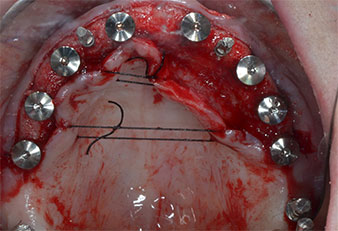

Compte tenu de la dureté relative de l’os (D2) à cet endroit, les sites recevant des implants de 10mm de long aux régions 11 et 21 ont été finalisés à l'aide d’une fraise de 4mm de diamètre, associée à un contre-angle chirurgical W&H WS-75 L, au moteur d'implantologie Implantmed de W&H ainsi qu’au module Osstell ISQ de W&H. En revanche, en raison de leur structure osseuse molle, les sites postérieurs ont été préparés en vue de l’obtention d’un diamètre final de 3mm à l'aide de l’insert Piezomed I3P. Les implants ont enfin été posés par voie transgingivale (Flap Less) pour obtenir l’ostéointégration dans un délai de trois mois (Figures 6-10). L'appareil existant a été maintenu sur quatre implants provisoires (Fig. 8).

Implant de 10mm au niveau du tissu

Fig. 6 : Un implant de 10mm au niveau du tissu est placé en région 21. L’implant en région 11 et les trois implants postérieurs gauches de 4mm sont déjà en place.